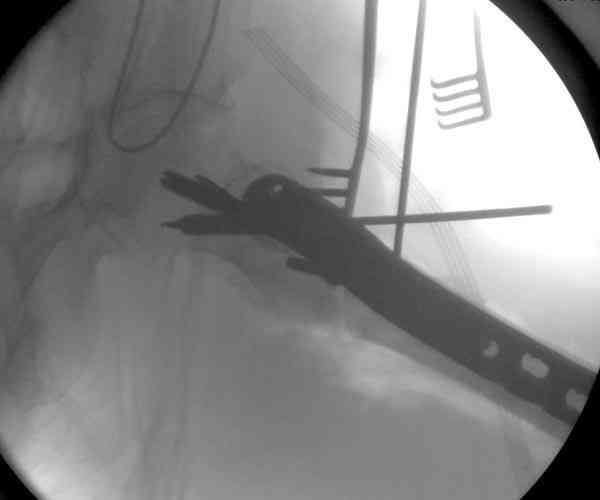

Из-за ослабленного латерального кортекса в проксимальной части бедра (прорезавшийся первичный неудачный штифт) штифт для фиксации не годится. Потом для установки современных блокирующих штифтов необходимы дополнительные оборудования и опыт применения.

Адекватная фиксация достигается длинным 95 градусным Blade Plate, где клинок пластины, связывая головку со средней трети бедра, создал бы условия для сращения.

Другой вариант пластины, это Synthes Proximal Locking Plate предназначенный для лечения прксимальных переломов бедра, где три шурупа: два 7.3 мм, введенных в головку под углом 95, 120 и 5.0 мм в 130 градусов, создают угловую стабильность.